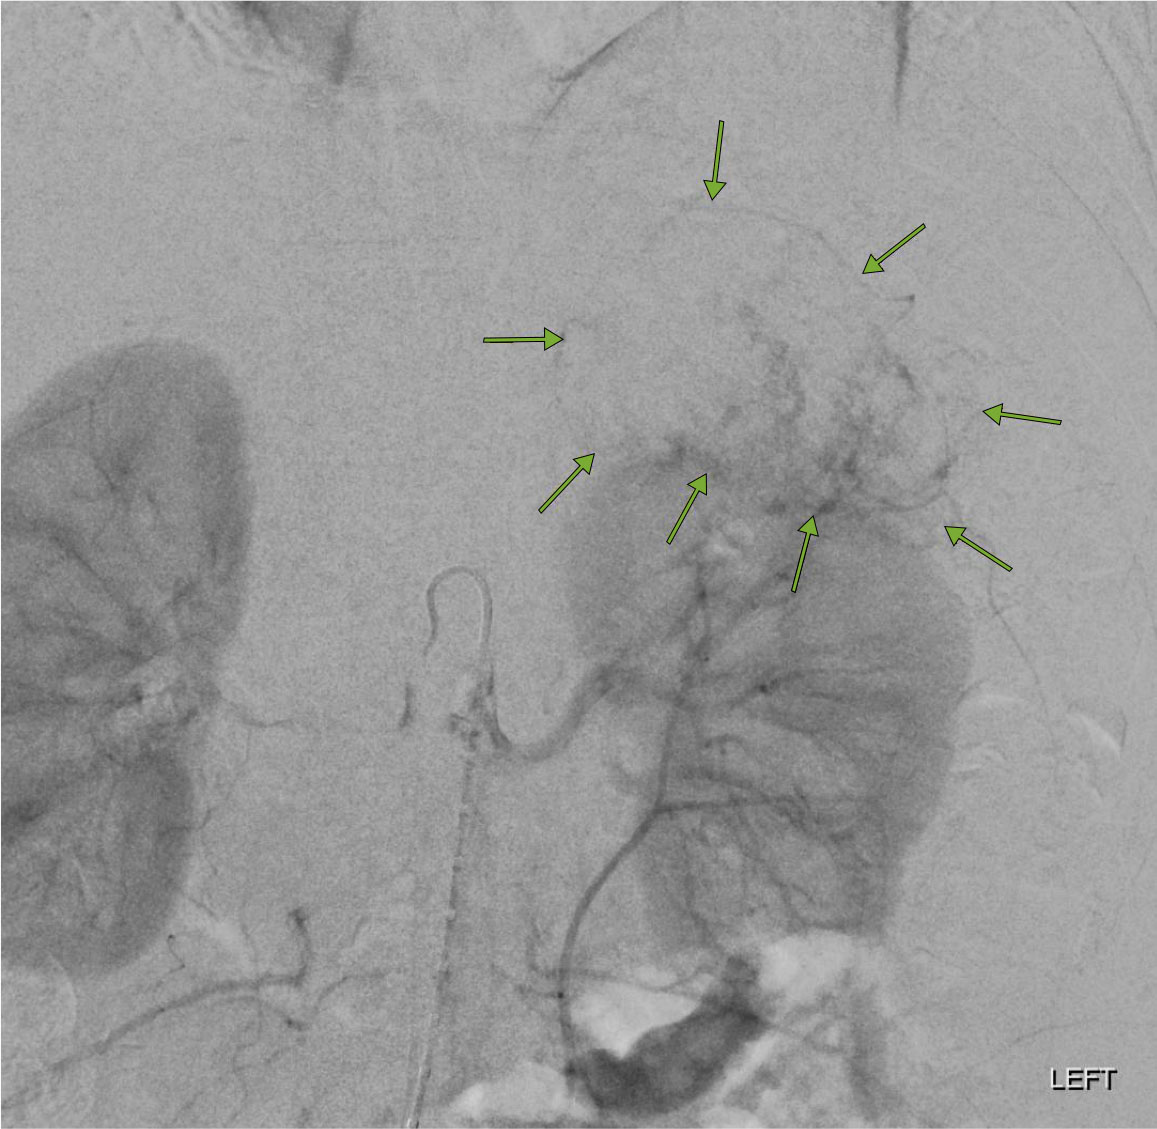

The AML was highly vascular as shown on this abdominal aortogram.

Our interventional radiology team performed an embolization procedure to cut off the blood flow to the AML. In this procedure the radiologist inserts a catheter into the aorta and then microcatheters thru the catheter into the tiny vessels feeding the tumor as seen on the image below.

Tiny particles are injected via the microcatheters into the vessel to embolize the tumor (tumor embolization). The left renal angiogram below demonstrates that the blood flow to the AML has been cut off resulting in a successful embolization.